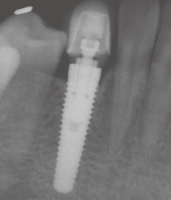

女性,22 岁, 现病史:外伤致33 脱落1 周后求诊,要求种植修复 既往史:无特殊

左下3缺失,牙龈略红肿,近远中距离可,对颌无伸长 X线示牙槽窝内空虚

术区常规消毒铺巾,碧蓝麻阻滞加浸润麻醉,牙槽脊顶切开翻瓣,尖钻定位,逐级备洞,植入牙槽窝清创后预备植牙窝,植入种植体(Replace Select®,4.3 mm×13 mm),唇侧缺损处填充自体骨屑。拧上愈合基台,穿龈愈合,严密缝合,常嘱术后4个月后复诊取模,2周后戴牙